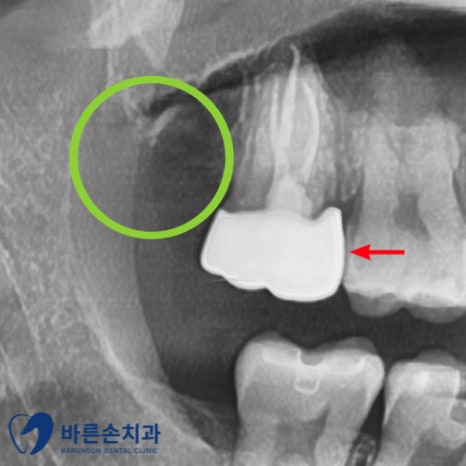

이제 오른쪽 아래 하이브리드 인레이 치료를 시작하였습니다.

마취를 하고 충치를 제거 한 후 치아를 부분적으로 삭제하여 본을 뜨고

3~4일 후 오셔서 보철물을 붙여드렸고 오른쪽 아래 치료가 끝납니다~